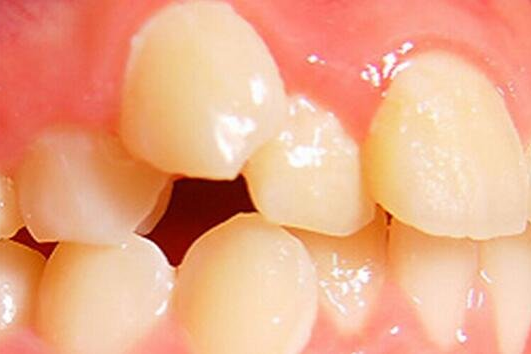

乳牙早失导致拥挤

间隙保持器为“新牙”萌出保留空间